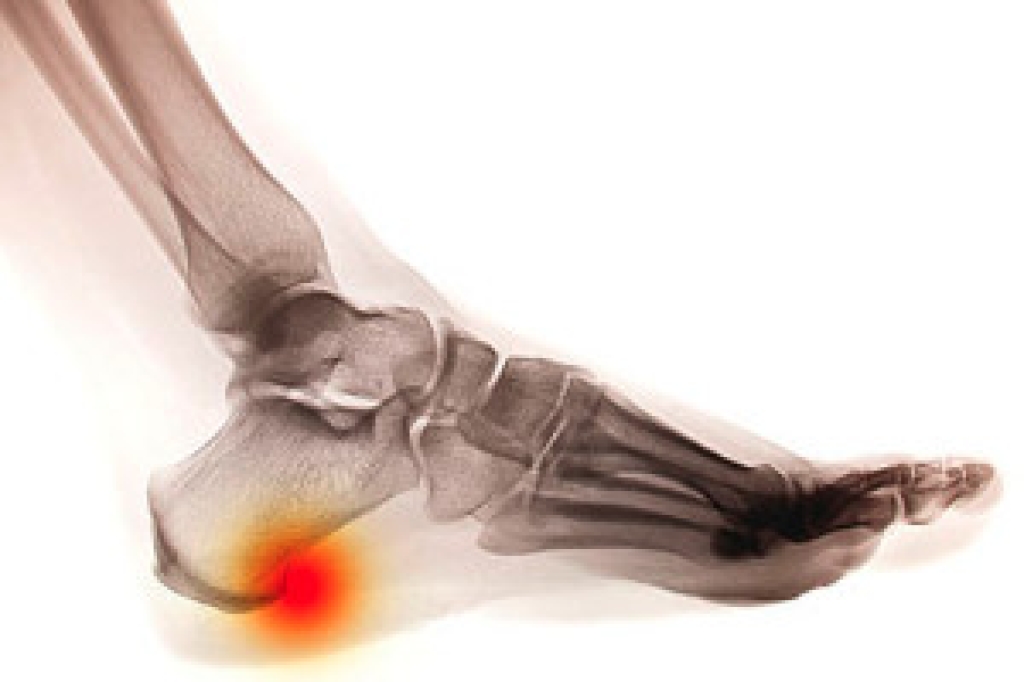

A sprained ankle occurs when the ligaments that support the ankle are stretched or torn, often caused by a sudden twist, uneven surfaces, sports activity, or a simple misstep. Symptoms include swelling, pain, and difficulty bearing weight. The ankle may look puffy or discolored and can feel stiff, weak, or unstable, with pain ranging from mild soreness to sharp discomfort during movement. A podiatrist can help by beginning with a detailed examination and imaging when needed to determine the severity of the injury. Early diagnosis is important to rule out fractures and guide proper care. Treatment may start with protection and swelling control, followed by bracing, footwear guidance, and targeted exercises to restore strength and flexibility. More severe sprains may require advanced care to prevent chronic instability. Proper treatment supports healing and reduces the risk of repeat injury. If you have a sprained ankle, it is suggested that you make an appointment with a podiatrist.

Although ankle sprains are common, they aren’t always minor injuries. If you need your ankle injury looked at, contact one of our podiatrists from Associates in Podiatry, PC. Our doctors can provide the care you need to keep you pain-free and on your feet.

How Does an Ankle Sprain Occur?

Ankle sprains are the result of a tear in the ligaments within the ankle. These injuries may happen when you make a rapid shifting movement while your foot is planted. A less common way to sprain your ankle is when your ankle rolls inward while your foot turns outward.

In many cases, the RICE method (Rest, Ice, Compression, and Elevate) is used to treat ankle sprains. However, you should see a podiatrist to see which treatment option would work best with your injury. In severe cases, surgery may be required.